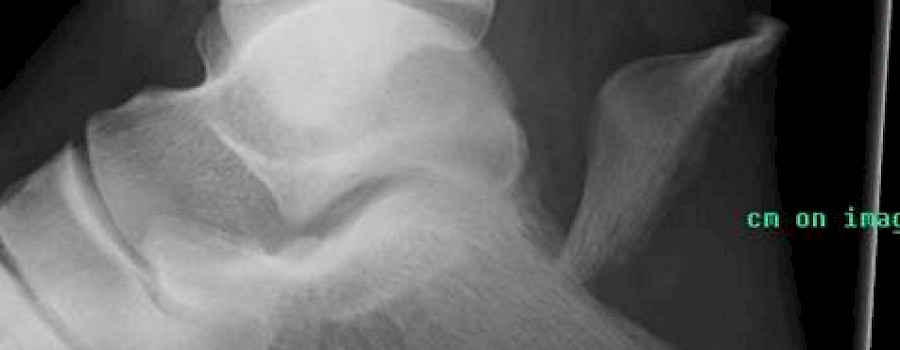

Fall: 46-jähriger Patient - von einer Laderampe gesprungen.